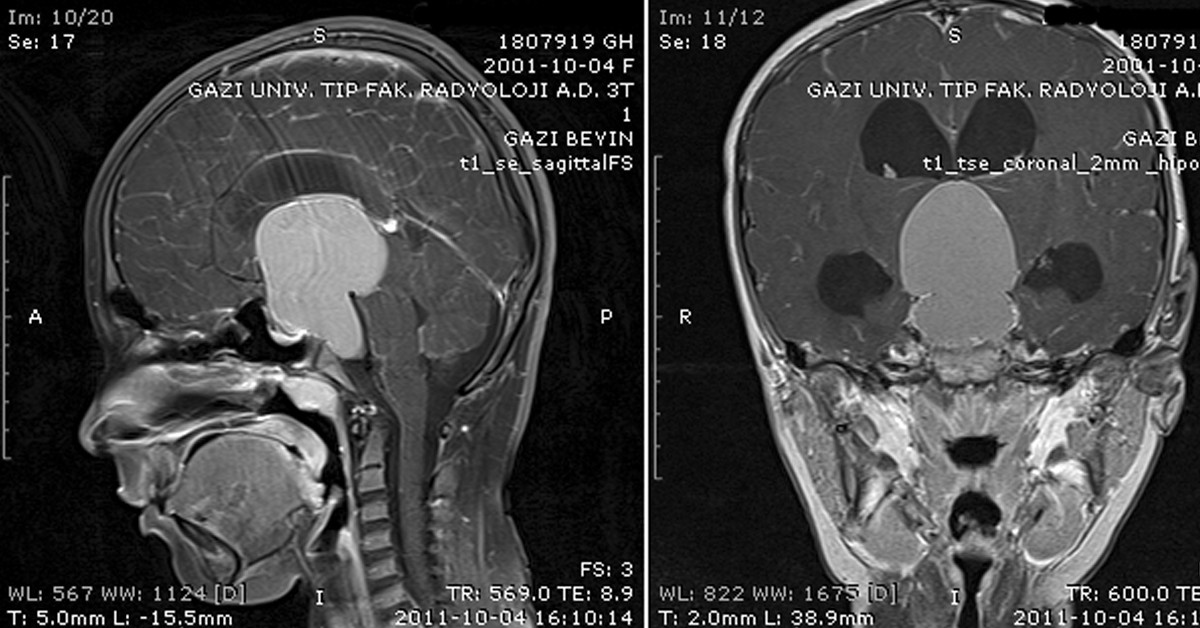

Genel olarak iyi huylu ve kötü huylu olarak ayrılan beyin tümörlerinde erken teşhis büyük öneme sahiptir. Her beyin tümörü öldürücü etkiye sahip olmadığı için doğru müdahale ve erken teşhis tümörlerin iyileştirilmesinde çok önemlidir. Erken teşhis ve tıbbın gelişmesi ile ortaya çıkan yeni tedavi yöntemleri sayesinde tümörler kontrol altına alınabilmektedir.

Beyin tümörleri, büyüyen ve ölen hücrelerin yerini yenileri almaktadır. Bu yenilenme aşamasında hücrelerin farklı bir yapıya bürünmesi, aşırı hücre çoğalması ya da yeni gelen hücrelerin ölmediği durumlarda bu hücreler kitle haline gelmeye başlamaktadır. Tümör olarak adlandırılan bu kitlelerin tam olarak nedeni ise bilinememektedir. Bununla birlikte, genetik faktörlerin ve radyasyona maruz kalmanın tümör oluşumunda önemli bir role sahip olduğu kabul edilmektedir.